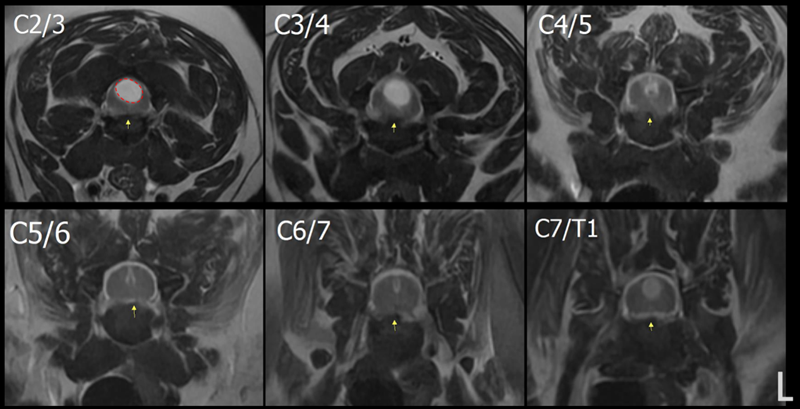

경추(C2–7 IVDS level)에서 퇴행성 다발성 디스크 돌출이 관찰되나, 횡단면상 유의미한 신경 압박을 보이는 부위는 없습니다.

C2/3 IVDS level에서 확장된 척수 중심관 면적은 43%로 측정되었으며, grade 2(33–60%)로 평가됩니다. ▼

(Severity of SM: grade 0 none, grade 1 <33%, grade 2 33–60%, grade 3 >60%)